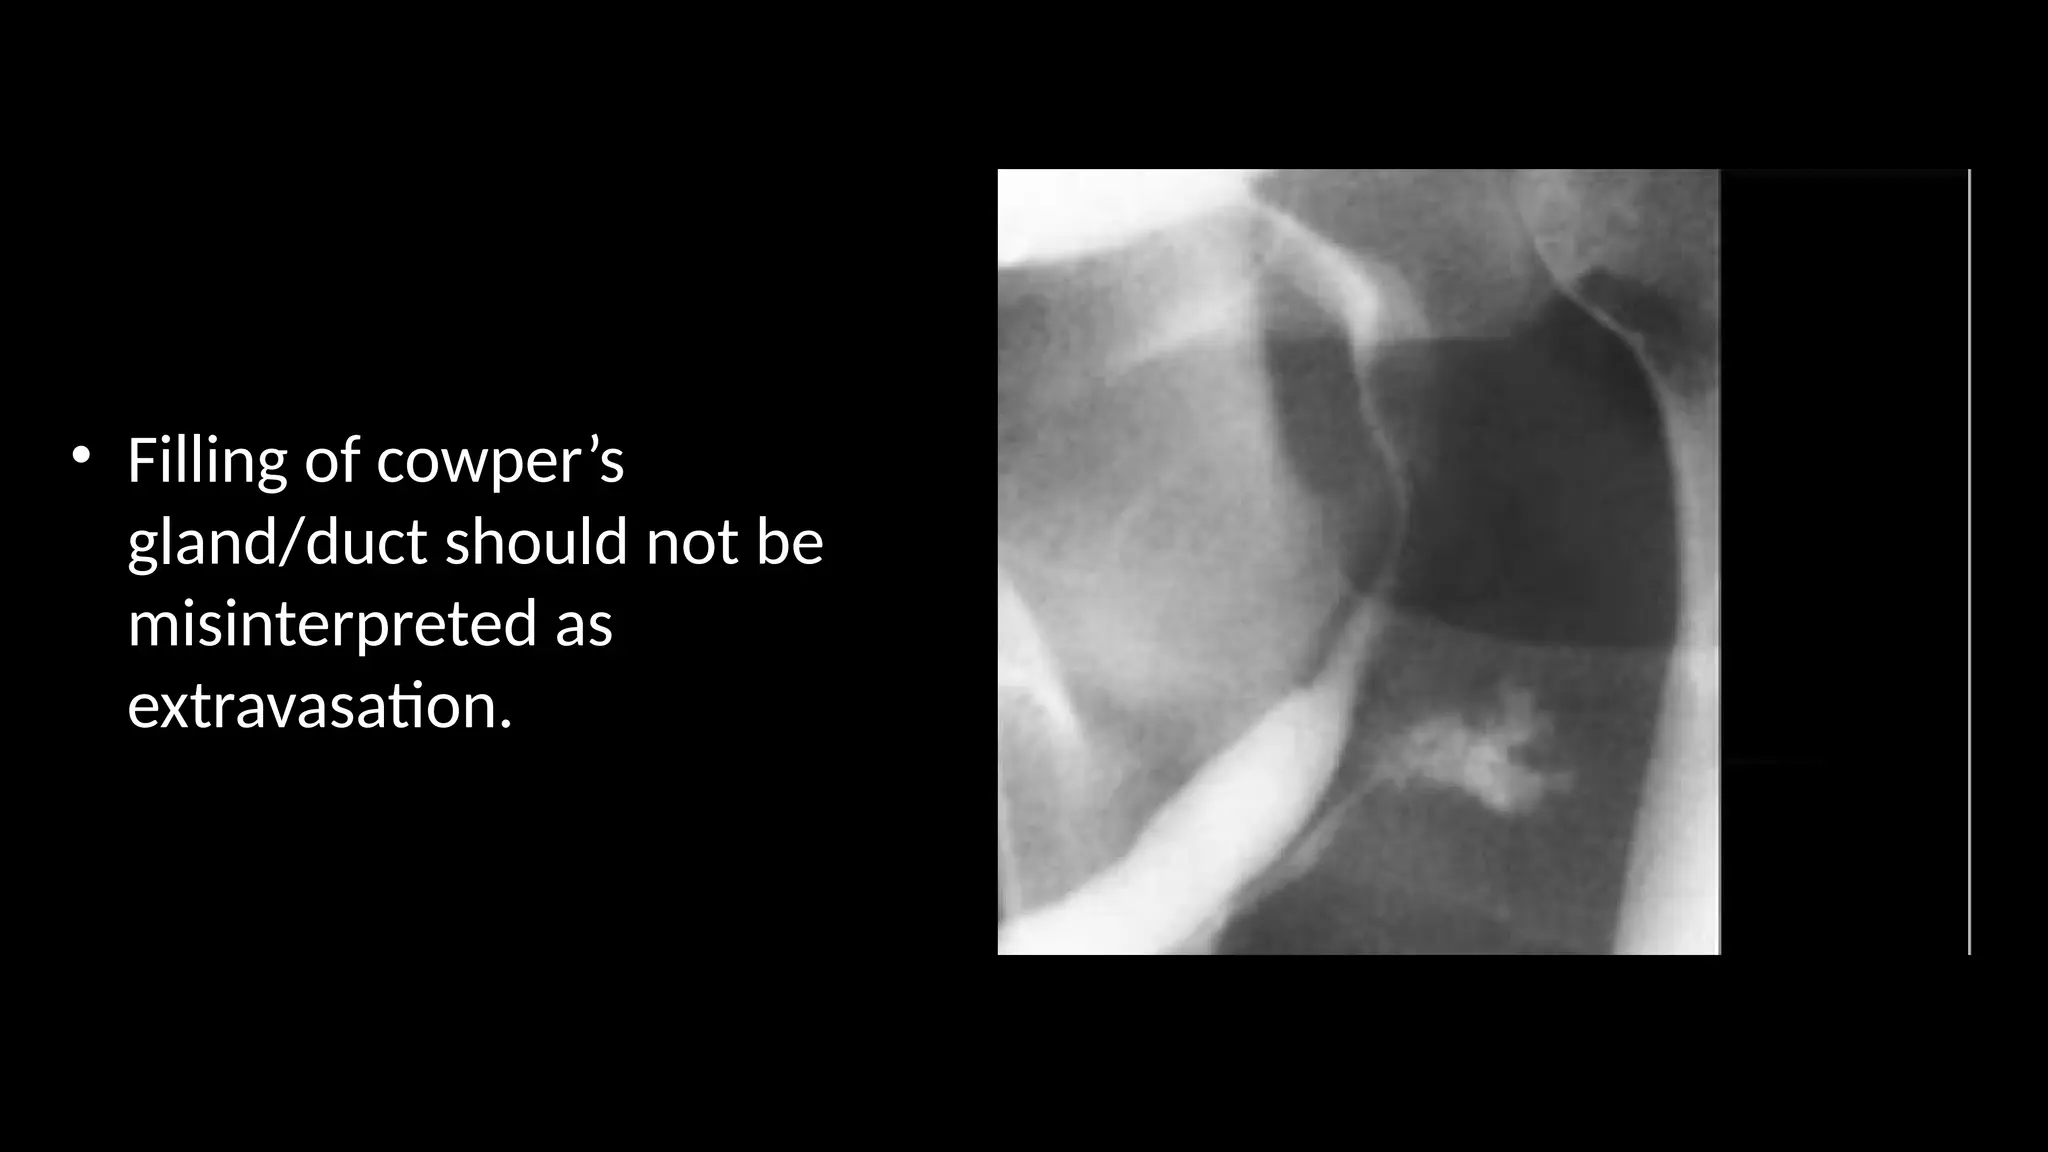

• Filling of cowper’s

gland/duct should not be

misinterpreted as

extravasation.

• Filling ofcowper’s gland/duct should not be misinterpreted as extravasation.